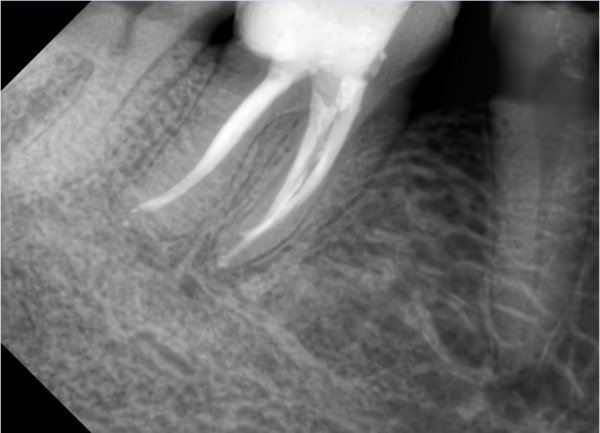

Посмотрите, пожалуйста, снимок. Есть ли карманы или нет и что может болеть?

Выложите снимок, я все прокомментирую.